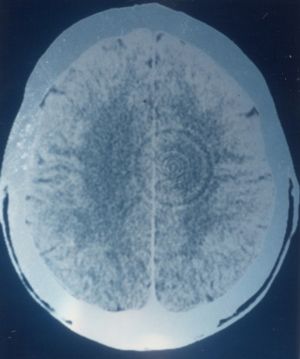

Beynin tüm vücudu kontrol ettiği varsayımıyla, Hammer, kanser hastalarının beyinlerinde belirgin değişiklikler olup olmadığını inceledi. Araştırması, hastaların CT taramalarında duygusal çatışmalar ve kanser türleriyle ilişkili belirgin beyin aktiviteleri gösterdi. Bu bulgular, belirli kanser türlerini beynin belirli bölgeleriyle ilişkilendirip, karşılık gelen duygusal ve biyolojik çatışmaları tanımlamasına yol açtı.

• Beyin Seviyesi: Çatışma şoku, beyinde belirli bir bölgeyi etkiler. BT görüntülerinde bu etki, keskin halkalar olarak görünür. Bu yapılar, Hamer Focus (HH) olarak adlandırılır ve çatışmanın doğasıyla ilişkilidir.

• Hamer Focus: Hamer Focus’un boyutu, DHS’nin yoğunluğuna bağlıdır. Bu yapıların varlığı, GNM’de ruhun organlarla iletişimini gösterir.

BT Görüntüleri ve GNM

GNM uygulamasında, beyin BT’si nihai tanı aracıdır. Kapsamlı bir analiz, DHS’nin doğası, çatışmanın yoğunluğu ve iyileşme süreci hakkında güvenilir sonuçlar sağlar. Hamer Odakları, ruh ve Biyolojik Özel Programların koordine edildiği kontrol istasyonudur.Not: GNM’de beyin taraması analizi, kontrast madde kullanılmadan yapılan BT’ye dayanır. Görüntüler, danışanın perspektifinden izlenir.

BEYİN SEVİYESİ: Çatışmanın (DHS) beyin üzerindeki etkisi, belirli beyin bölgelerindeki nöronlarda hafif hasara neden olur. Ruhsal ve organ iyileşmesi ile paralel olarak, etkilenen nöronlar da onarım sürecine girer. PCL-A aşamasında, beyin dokusunu korumak amacıyla bir beyin ödemi oluşur. Ödemin boyutu, çatışmanın yoğunluğu ve DHS anında oluşan Hamer Odağı‘nın boyutuna bağlıdır.

PCL-A aşamasında, keskin hedef halkalar (bkz. çatışma aktif faz) ödem içine batırılır ve BT taramasında koyu (hipodens) olarak görünür; bu, PCL-B ile karşılaştırılabilir. SYNDROME’a bağlı su tutulumu ödemin boyutunu artırabilir. Konvansiyonel tıp, bu ödemi yanlışlıkla “beyin tümörü” olarak teşhis edebilir.